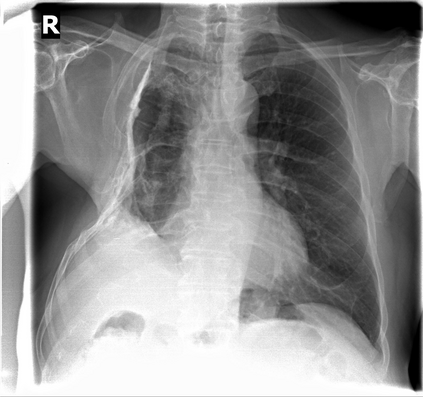

The evaluation of infectious disease processes on radiologic images is an important and challenging task in medical image analysis. Pulmonary infections can often be best imaged and evaluated through computed tomography (CT) scans, which are often not available in low-resource environments and difficult to obtain for critically ill patients. On the other hand, X-ray, a different type of imaging procedure, is inexpensive, often available at the bedside and more widely available, but offers a simpler, two dimensional image. We show that by relying on a model that learns to generate CT images from X-rays synthetically, we can improve the automatic disease classification accuracy and provide clinicians with a different look at the pulmonary disease process. Specifically, we investigate Tuberculosis (TB), a deadly bacterial infectious disease that predominantly affects the lungs, but also other organ systems. We show that relying on synthetically generated CT improves TB identification by 7.50% and distinguishes TB properties up to 12.16% better than the X-ray baseline.